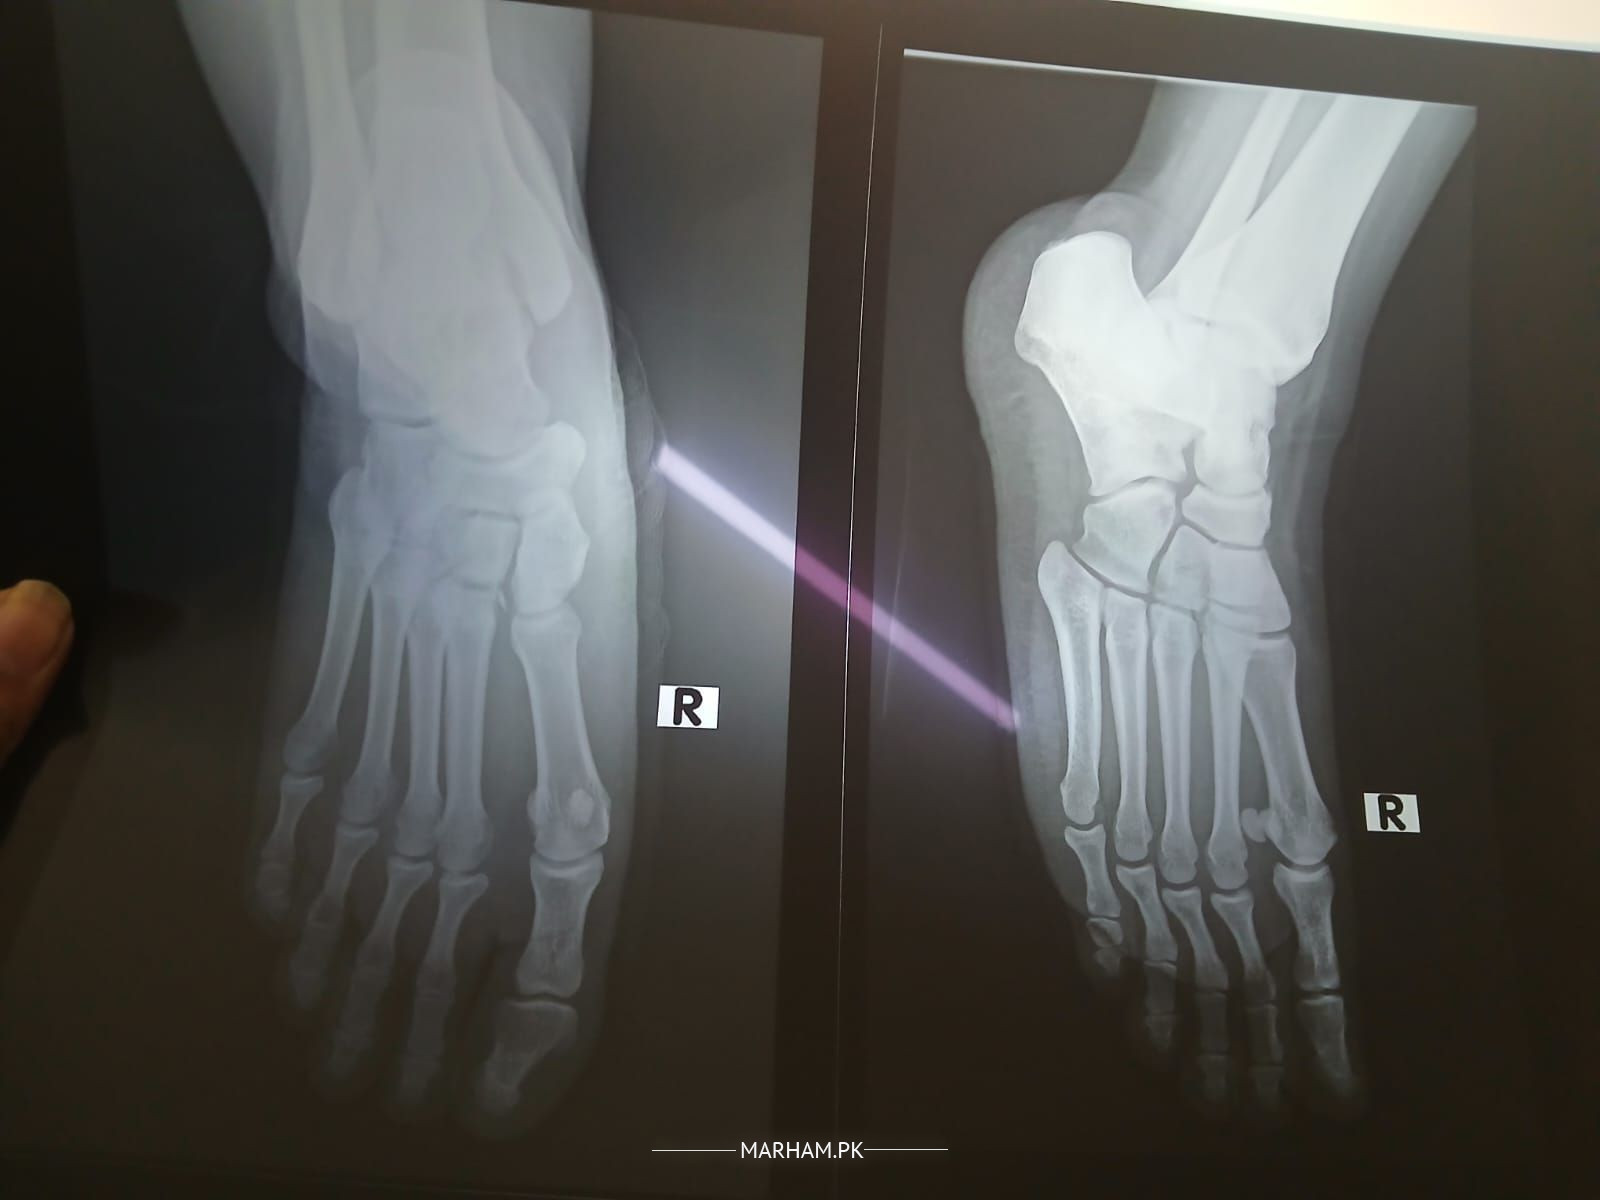

she fell 3 days ago and had the tissues damaged of right foot. it's been 3 days, there's still swelling and can't walk etc. she is having tonoflex and nuberal forte. when will she get alright? and anything else she should do right now?

most probably lisfranc injury

fracture nahi hai Alhumdolillah .

get weight bearing xrays, get proper examination, don't bear weight on this foot, it will be painful & risk of further damage to the foot..